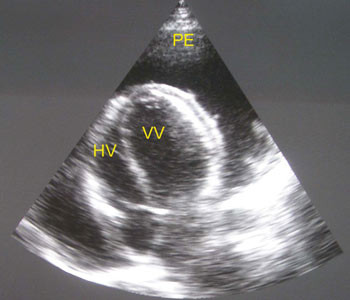

Hivpositiv 41 år gammel mann ble innlagt etter to uker med økende tungpust og ubehag i brystet. Ved undersøkelse var han medtatt, blodtrykk ble målt til 95/65 mm Hg, puls 125/min, respirasjonsrate 44/min. Han hadde ortopné og halsvenestuving. Lungene var klare ved auskultasjon, og det ble påvist hepatomegali uten perifere ødemer. Hjertetonene var fjerne, det var ingen bilyd, og ictus var ikke palpabel. EKG viste sinustakykardi. Røntgen thorax viste uttalt kardiomegali (fig 1a).

De mest aktuelle differensialdiagnosene ble vurdert å være dilaterende/hivassosiert kardiomyopati eller tuberkuløs perikarditt. Røntgen thorax alene er ikke nok til å skille mellom tilstandene (fig 1b). Legen ved lokalsykehuset sto overfor et dilemma: Skulle han satse på diuretika eller gi væske? Diuretika kan være svært uheldig for en pasient med perikardvæske og truende tamponade, som er avhengig av å opprettholde fyllingstrykket. De kliniske tegnene og et normalt EKG gjorde at mistanken om perikardeffusjon var stor.

Pasienten ble overført til regionssykehus. Ekkokardiografi bekreftet en svær perikardeffusjon med fibrintråder typisk for tuberkuløs perikarditt (fig 2), og tegn på hjertetamponade. Det ble gjort perikardiocentese og tappet 750 ml blodig perikardvæske. Tilstanden bedret seg umiddelbart, og pasienten ble på empirisk grunnlag gitt antituberkuløs behandling og prednisolon.

Denne sykehistorien er vanlig i land der hiv og tuberkulose er svært utbredt. Den viser at differensialdiagnostikken ved kardiomegali kan være vanskelig, og at ekkokardiografi, når undersøkelsen er tilgjengelig, ofte er avgjørende for diagnose og behandlingsvalg. Dessverre er tilgangen på kardiologisk ekspertise og ekkokardiografi dårlig eller ikke-eksisterende for store deler av befolkningen i Afrika.